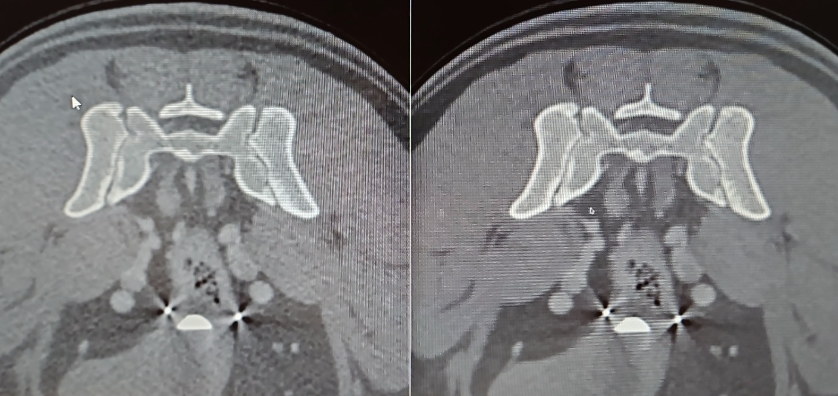

Kopf und Wirbelsäule: Auch in diesem Segment sind CBCT Einsätze aussagekräftig und erfolgreich – hier werden Scans zur genauen Diagnosestellung vom MRT abgelöst, wenn auch die zukünftige Optimierung mittels künstlicher Intelligenz die Bildqualität nochmals absehbar erhöhen wird (Abb. 7 & 8).

Vergleichende Darstellung eines KI optimierten Kopfscans einer Katze mit einem destruktiven Tumor im Kopfbereich (links original, rechts KI gestützt).